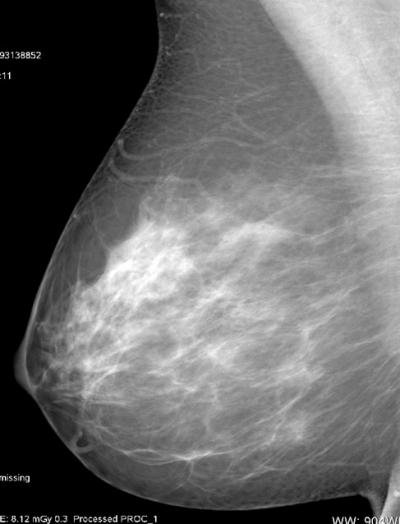

CHICAGO – Automated breast density measurement is predictive of breast cancer risk in younger women, and that risk may be related to the rate at which breast density changes in some women as they age, according to research being presented today at the annual meeting of the Radiological Society of North America (RSNA).

Breast density, as determined by mammography, is already known to be a strong and independent risk factor for breast cancer. The American Cancer Society (ACS) considers women with extremely dense breasts to be at moderately increased risk of cancer and recommends they talk with their doctors about adding magnetic resonance imaging (MRI) screening to their yearly mammograms.

For the new study, Dr. Perry and colleagues compared breast density and cancer risk between younger and older women and analyzed how the risk relates to changes in breast density over time. The study group included 282 breast cancer cases and 317 healthy control participants who underwent full-field digital mammography, with breast density measured separately using an automated volumetric system.

"In general, we refer to breast density as being determined by mammographic appearance, and that has, by and large, in the past been done by visual estimation by the radiologist—in other words, subjective and qualitative," Dr. Perry said. "The automated system we used in the study is an algorithm that can be automatically and easily applied to a digital mammogram, which allows an objective and, therefore, quantitative density measurement that is reproducible."

Breast cancer patients showed higher mammographic density than healthy participants up to the age of 50. The healthy controls demonstrated a significant decline in density with age following a linear pattern, while there was considerably more variability in density regression among the breast cancer patients.

"The results are interesting, because there would appear to be some form of different biological density mechanism for normal breasts compared to breasts with cancer, and this appears to be most obvious for younger women," Dr. Perry said. "This is not likely to diminish the current ACS guidelines in any way, but it might add a new facet regarding the possibility of an early mammogram to establish an obvious risk factor, which may then lead to enhanced screening for those women with the densest breasts."

For instance, some women might undergo a modified exposure exam at age 35 to establish breast density levels, Dr. Perry noted. Those with denser breast tissue could then be followed more closely with mammography and additional imaging like MRI or ultrasound for earlier cancer detection and treatment.